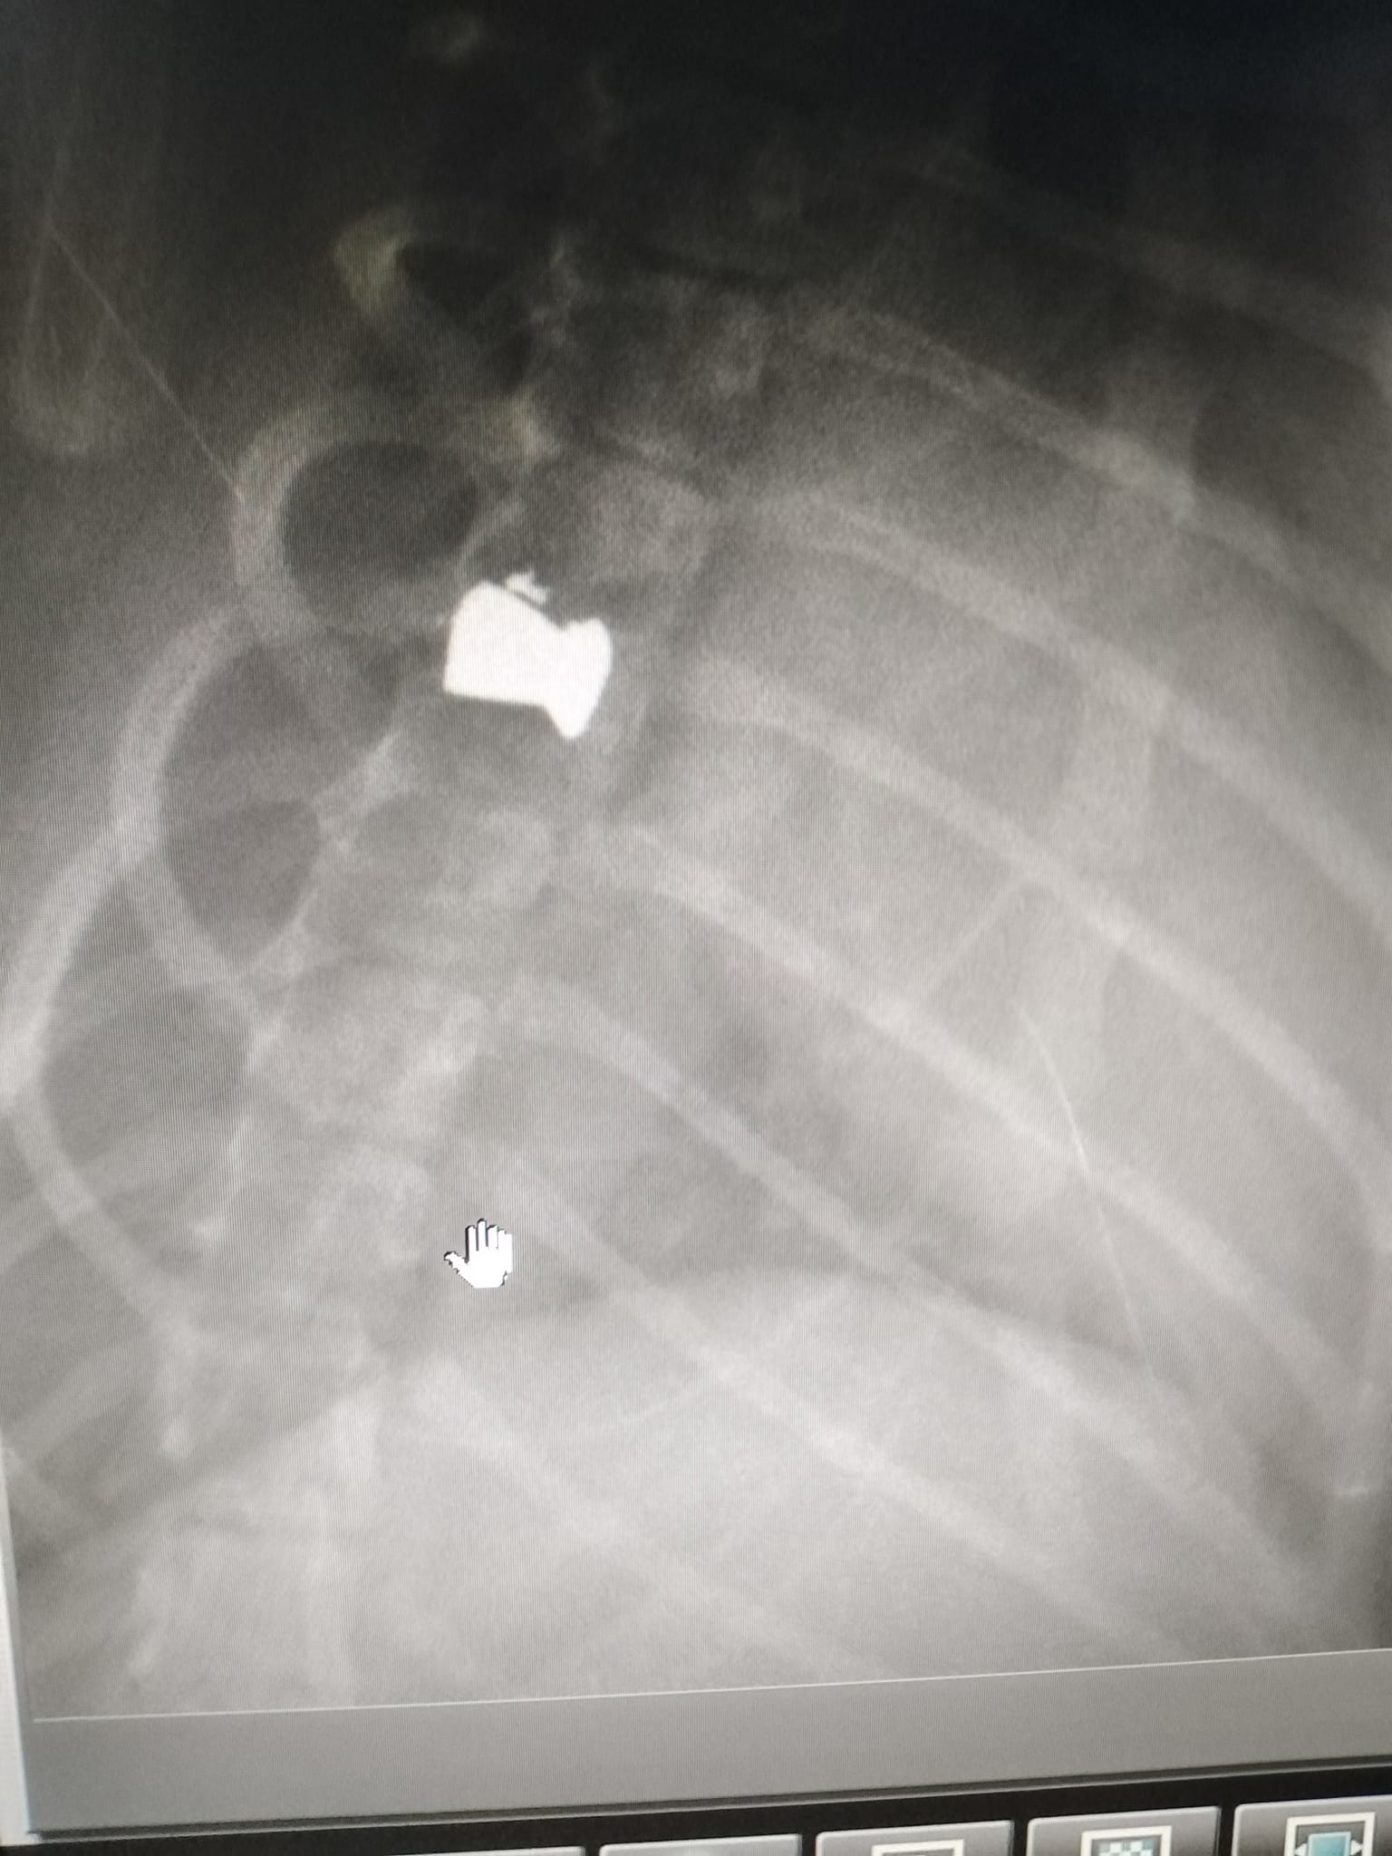

Οι άνθρωποι της Φιλοζωϊκής μετέφεραν το ανήμπορο γατάκι στην κτηνίατρο κα Βαλυρακη και από τις ακτινογραφίες, διαπιστώθηκε ότι είναι πυροβολημένο με αεροβόλο.

Θέλουμε να επιστήσουμε την προσοχή των συμπολιτών μας, καθώς, όπως γνωρίζουμε πλέον από πλήθος επιστημονικών δεδομένων, αυτού του είδους οι κατά συρροή κακοποιητές ζώων, σπάνια σταματούν στα ζώα. Επιπλέον κινδυνεύουν και άνθρωποι από “αδέσποτες” σφαίρες. Ελπίζουμε όσοι γνωρίζουν, συγκαλύπτουν ή και ενθαρρύνουν τέτοιου είδους άθλιες συμπεριφορές να αναλάβουν την προσωπική τους ευθύνη απέναντι στο κοινωνικό σύνολο πριν να είναι αργά. Bullet! Το σημερινό περιστατικό. Βρέθηκε στο πεζοδρόμιο, σε κεντρικό σημείο της πόλης, ανίκανος να κουνηθεί, μια μπουκίτσα 5 μηνών. Τον μεταφέραμε στην κα Βαλυρακη και από τις ακτινογραφίες, διαπιστώθηκε ότι είναι πυροβολημένος με αεροβόλο. Μία σφαίρα, έχει καρφωθεί στη σπονδυλική του στήλη. Ο Bullet δεν πέθανε αλλά είναι πλέον ανάπηρος γιατί κάποιος αποφάσισε ότι δεν αξίζει να ζει. Θα χρειάζεται άδειασμα κύστης και περιμένουμε απάντηση, αν υπάρχει ελπίδα να ξαναπερπατήσει μετά από χειρουργείο”.